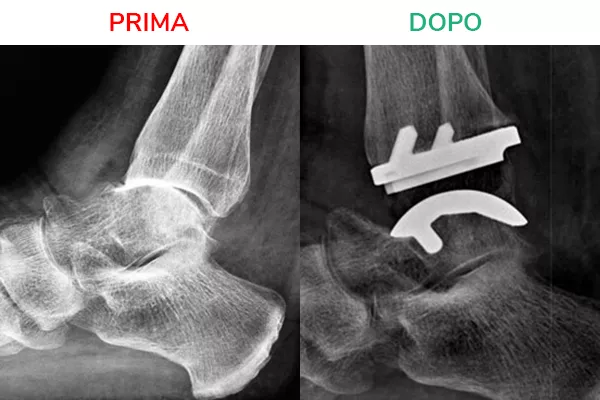

Radiografia in movimento

La radiografia in movimento mostra lo spazio articolare ripristinato e la distanza tra tibia e astragalo. Il movimento risulta fluido e scorrevole, simile a quello fisiologico. Il risultato che si deve ottenere al termine dell’intervento di Protesi di Caviglia è la normale mobilità della caviglia in flesso-estensione.